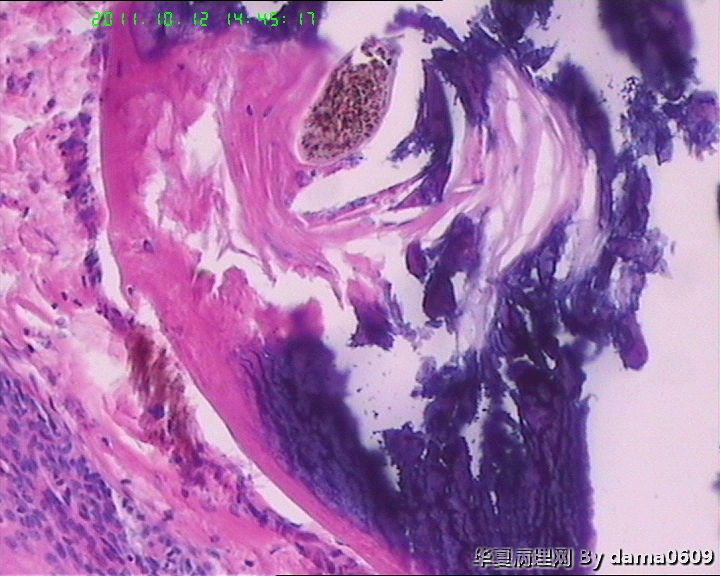

女,42岁,右眼外上方皮下肿物4年。

送检:椭圆形肿物,v:0.5x0.5x0.4cm,实性,灰白色,质软。

毛发腺瘤

毛发型角质囊肿伴局灶钙化?

看起来,是否要考虑毛发上皮瘤?

皮肤及附属器的肿瘤学生见得少,这一例发病部位和大体上符合“毛发上皮瘤”,但静下上好像要求由两层基底样细胞条索样排列和增生的间质构成,具体记不清了,也不知道对不对,我这例不见那样的典型结构啊!!

镜下大部分都是毛囊结构,要考虑毛囊痣。